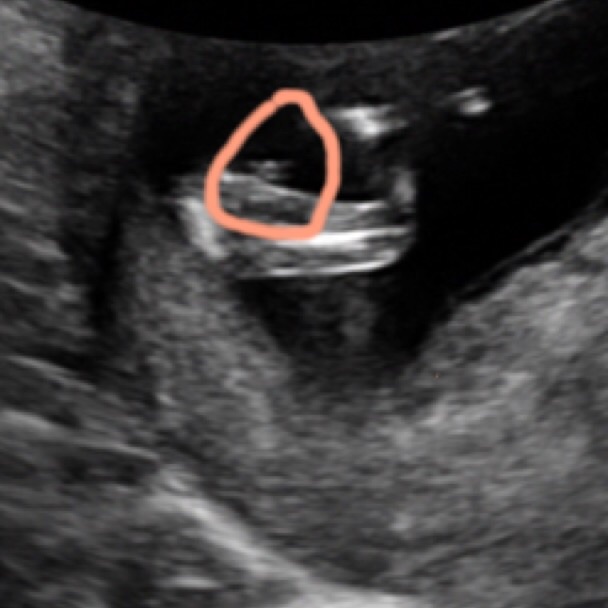

Can you take the drawing off plz :)

Thinking boy

Looking like a boy.